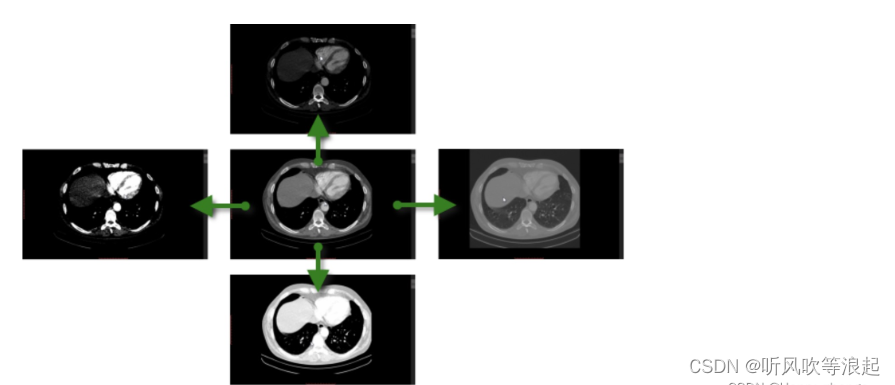

就如下面图像,原始的医学图像可能是最右面的图像,经过windowing方法,变成最左边的,当然分割变得容易喽